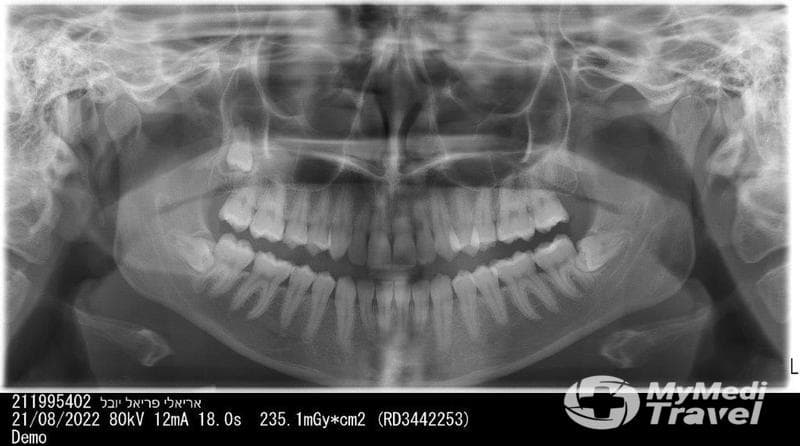

What does Wisdom Teeth Israel offer patients?